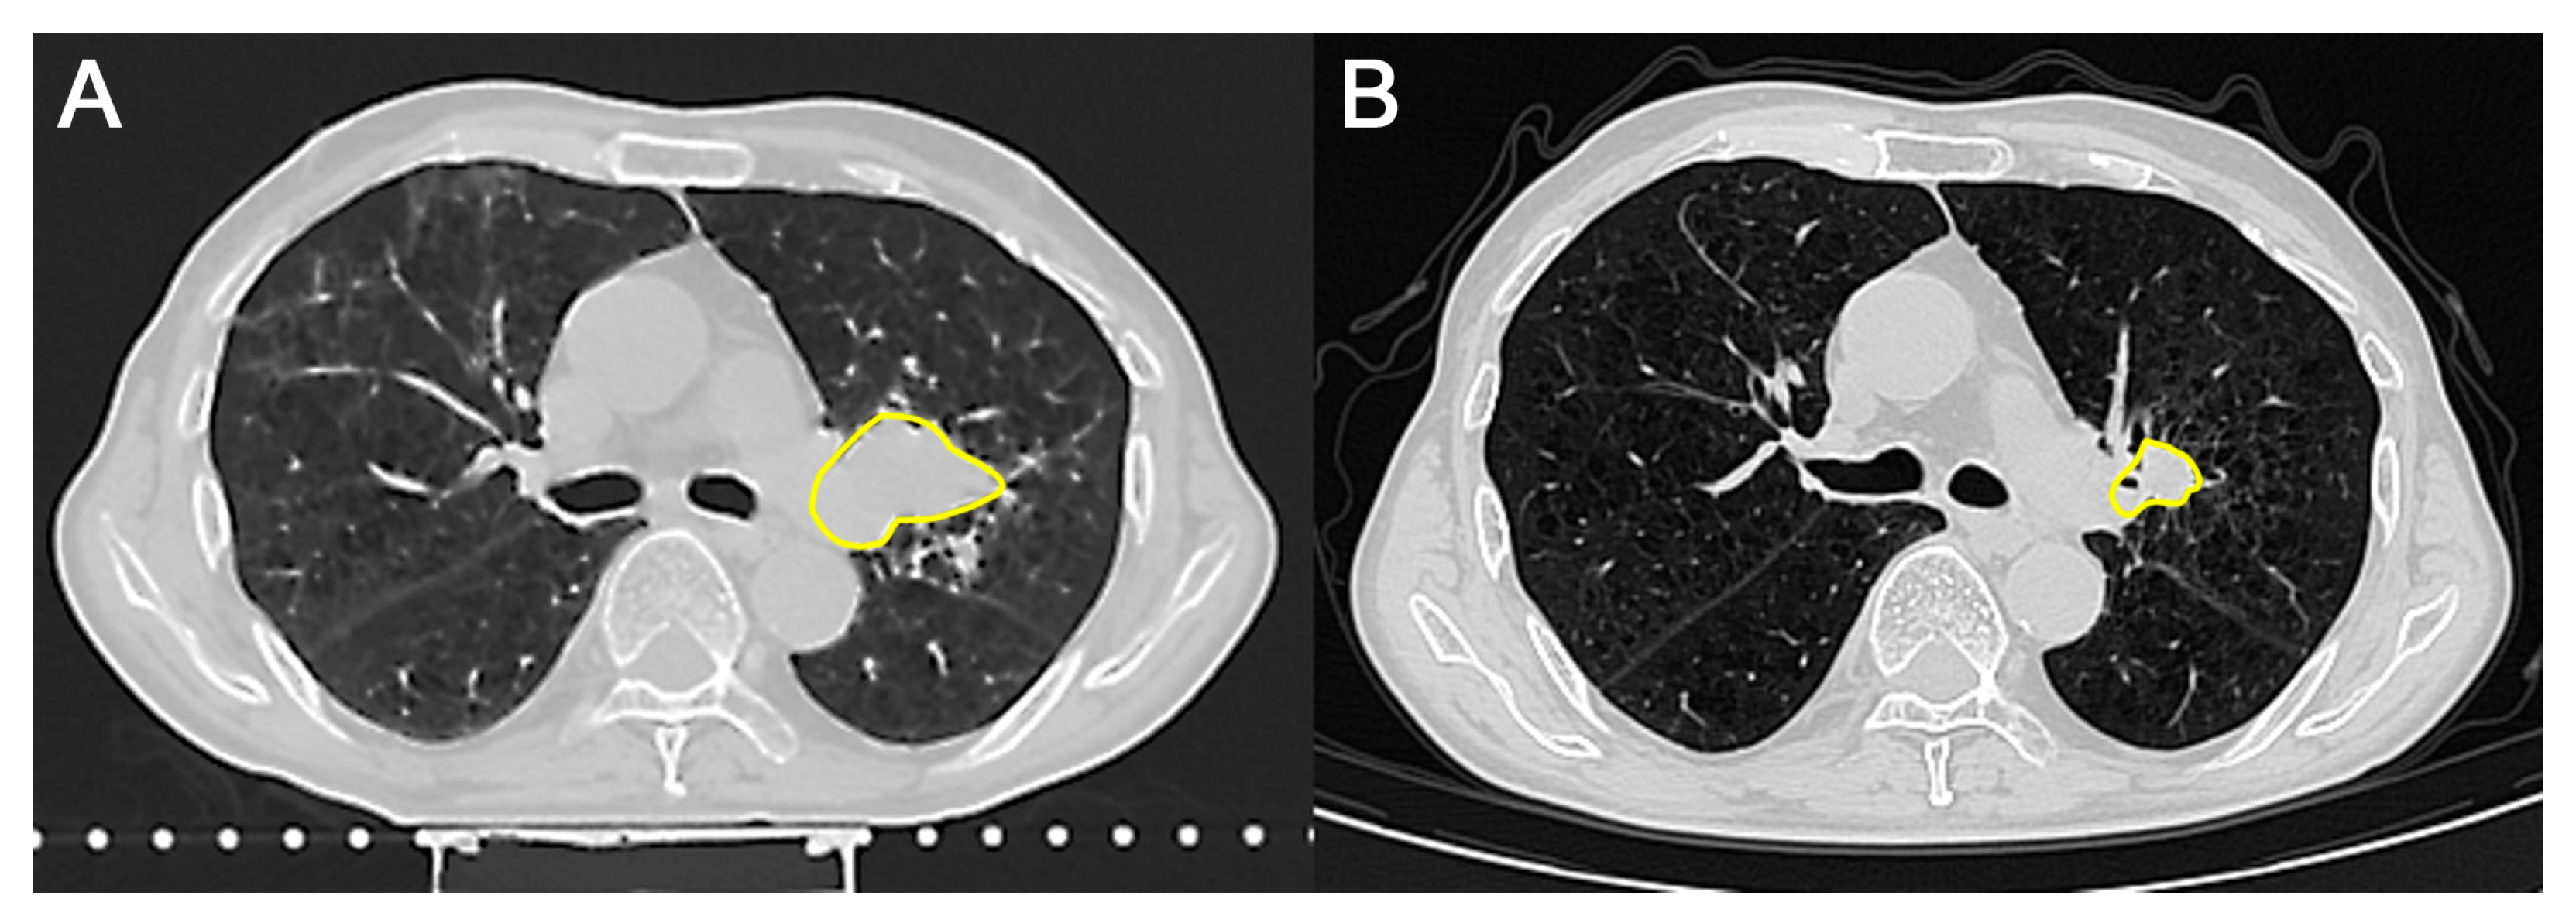

| 8 October 2024 | Chest CT scan shows negative dynamics due to an increase in the size of the mass. Single adenopathy of the tracheobronchial lymph nodes on the left. Consultation by radiologist. Circulating Tumor Cell (CTC) measurement (before combined treatment). |

| 19 December 2024 | Chest CT scan shows positive dynamics; the tumor decreased in size. CTC measurement (after combined treatment). |